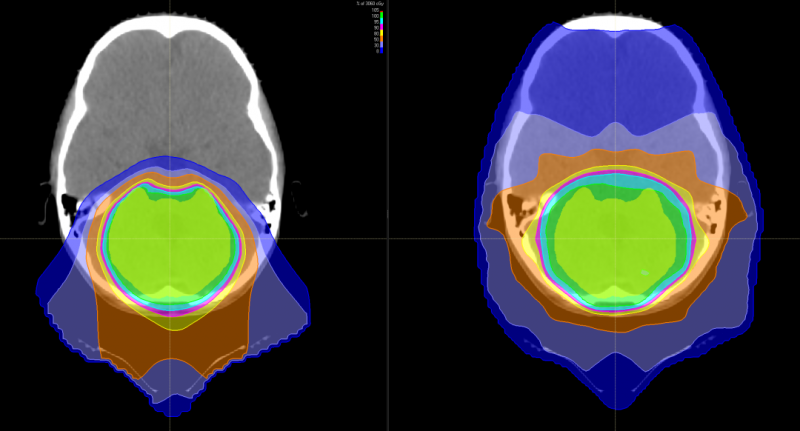

有研究表明,儿童神经母细胞瘤使用质子治疗的最大效益在于减少脑部正常组织构造的损伤,进而降低长期伤害。质子治疗是一种比其他任何形式的放射治疗更准确,更精确地靶向肿瘤,同时保留健康组织,目前全球最先进的一种放疗技术。通过质子治疗,可以最大限度地避免靶标外部的绝大多数不必要的辐射。

与传统形式的辐射相比,质子束会到达肿瘤内部的精准位置而不是沿着光束离开人体的路径释放大部分辐射剂量。实际上,质子没有肿瘤之外的辐射“退出剂量”,这意味着质子停在肿瘤上,不会继续伤害身体的健康部位。

使用质子(左)与X射线治疗(右) 质子治疗对周围重要器官损伤更少